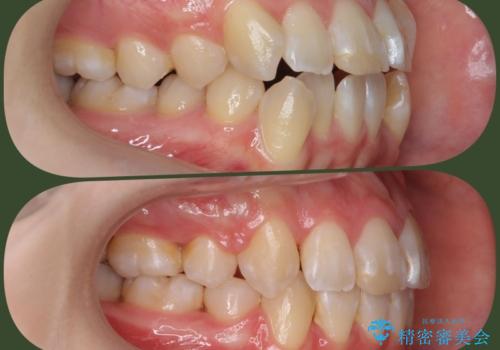

[ インビザライン ] 目立たないマウスピース矯正で、前歯のがたつきをきれいにしたい

- 前歯のがたつきを「装置の目立つワイヤーではなく、マウスピースで治療したい。」と希望され来院されました。

シミュレーションを作成した結果、26枚以下のリーズナブルなモデレートプランが適応であることがわかりました。

費用を抑えられただけでなく、治療期間も約半年と短期間で治療を終了することができました。